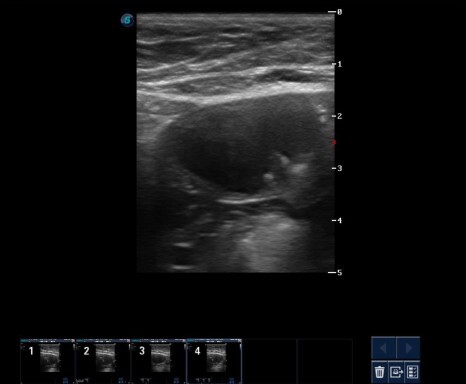

혈뇨 증상으로 내원한 아이입니다.

감별 진단을 위해 방광 초음파 검사, 방사선 검사,

소변 검사를 진행하였습니다.

초음파 검사에서는 혈괴 또는 슬러지(sludge)로 의심되는 물질을 관찰할 수 있었습니다.

항생제 투약 2주 후 혈뇨가 없어지고 초음파 검사상 방광 상태도 호전된 것을 확인할 수 있었습니다.